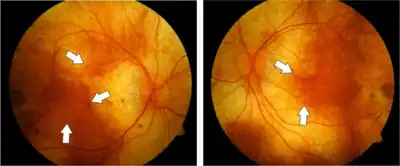

A diagnosis of choroideremia can be made based on family history, symptoms and the characteristic appearance of the fundus.[10] However, choroideremia shares several clinical features with retinitis pigmentosa, a similar but broader group of retinal degenerative diseases, making a specific diagnosis difficult without genetic testing. Because of this choroideremia is often initially misdiagnosed as retinitis pigmentosa.[11]